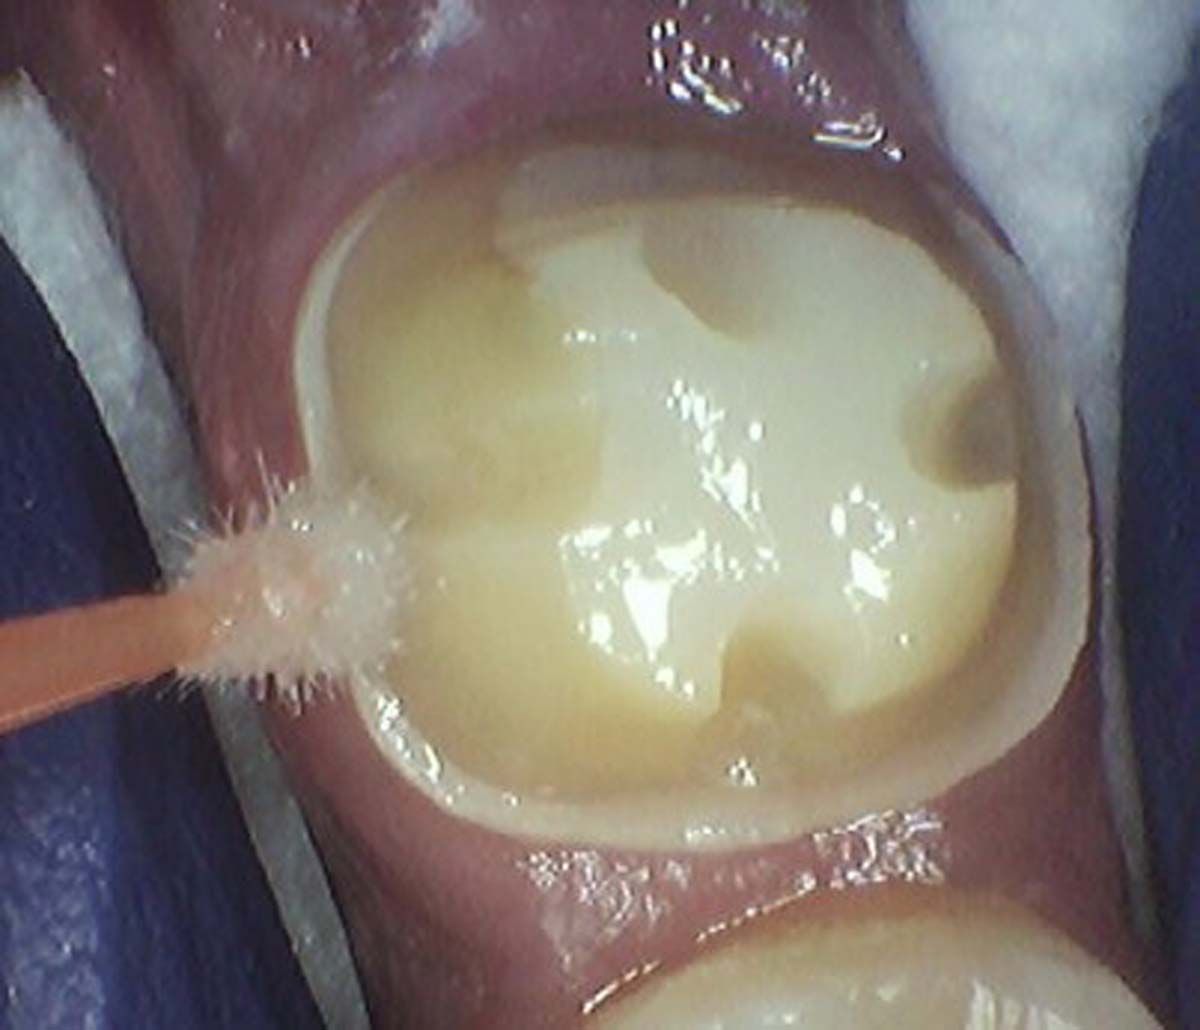

Infection was identified on pariapical x-rays.

A look at patient's periapical x-rays.